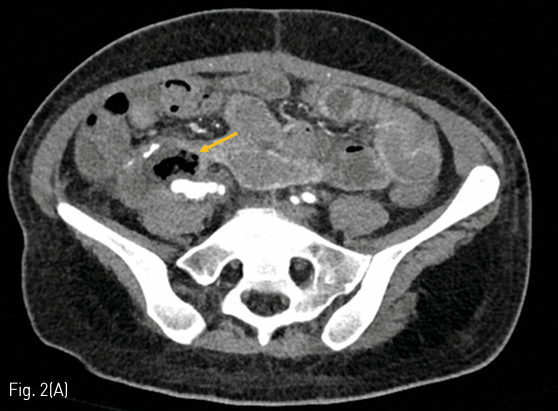

혈관조영술 상 right proximal external iliac artery에 saccular pseudoaneurysmal dilatation 이 보였다 (Fig. 3A). 이에 대해 8 mm x 3 cm stent graft (SEAL GRAFT EXTENSION, S&G Biotech, Seongnam, Korea)를 삽입하였으며 (Fig. 3B), 8mm x 20mm and 10mm x 20mm Mustang balloon (Boston Scientific, Marlborough, MA, USA)로 post stenting ballooning을 시행하였다. Completion iliac angiography 상 작은 residual pseudoaneurysmal lesion이 있으나 active bleeding 소견은 없었다(Fig. 3C).

Fig 3B

(A, B, C) Stent graft was placed for pseudoaneurysm of right external iliac artery. Completion angiography showed a small residual pseudoaneurysmal lesion without evidence of active bleeding.